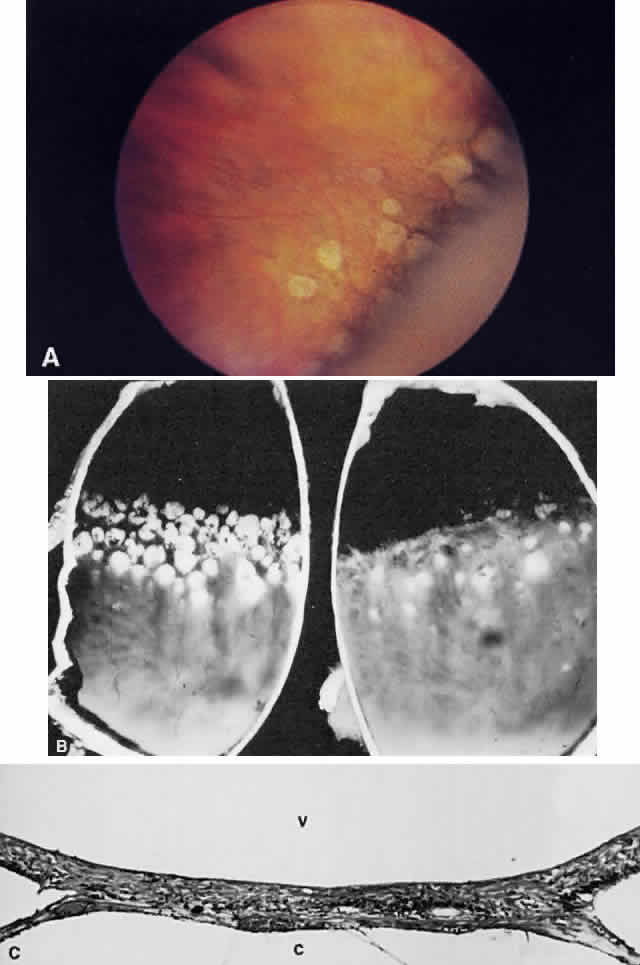

Typical cystoid degeneration involves the formation of cyst-like spaces at the level of the outer plexiform layer (Blessig-Iwanoff cysts) (Fig. 59). These are common lesions, present in most persons from the first decade of life. These “cysts” appear to become more numerous with age. Coalescence of these cysts may result in “senile” retinoschisis.23 Reticular cystoid degeneration involves a disruption at the level of the nerve fiber layer. It is located frequently just posterior to the area of typical cystoid degeneration. A network of fine, branching blood vessels is seen commonly over the surface of reticular cystoid degeneration.

Fig. 59. A. Typical cystoid degeneration of the peripheral retina with cyst-like spaces in the outer plexiform layer (Blessig-Iwanoff cysts). These cysts sometimes coalesce, and the inner layer breaks down to form a hole. B. Peripheral cystoid degeneration with atrophic holes. (A, courtesy of Ralph C. Eagle Jr, MD, Philadelphia, PA. B, courtesy of William Tasman, MD, Philadelphia, PA).

Degenerative or senile retinoschisis involves a splitting of the retina at the level of the outer plexiform layer for a distance of at least one disc diameter. As seen ophthalmoscopically, degenerative retinoschisis frequently has a “beaten metal” appearance, and fine, white dots may be seen within the cavity. These dots are thought to represent columns of Müller cells that have been stretched to the point of rupture: the clinically observed dots are Müller cell remnants that remain adherent to the internal limiting membrane. These Müller columns are believed to be responsible for the unevenness of the outer schisis surface; the inner surface is typically smooth. Large holes in the outer wall of the schisis cavity (by convention, “outer” refers to the scleral side of a retinal lesion whereas “inner” refers to the vitreous side of the retina) are frequently observed (Fig. 60), although smaller inner layer holes are less common. The presence of holes in both the inner and outer walls of a schisis cavity creates a pathway from the vitreous to the subretinal space, and a rhegmatogenous retinal detachment may develop.

Fig. 60. A. Photomicrograph of a retinoschisis cavity with a hole in the outer layer (OL). The inner layer (IL) is intact. Typical peripheral cystoid degeneration is present (arrow). B. Outer wall holes in a patient with senile retinoschisis. Notice the pocked marked appearance of the outer wall layer peripheral to the holes. (B, courtesy of William Benson, Philadelphia, PA, Wills Eye Atlas of Ophthalmology. Lippincott-Raven Fig 4-58, 1996)

In contrast to lattice degeneration, which affects the inner retinal layers, paving stone degeneration (cobblestone degeneration, peripheral chorioretinal degeneration) affects the outer retinal layers.24 Ophthalmoscopically, paving stone lesions appear as well-demarcated concave zones of depigmentation (Fig. 62A and B). Frequently, the depigmentation is so marked that the larger, outermost choroidal vessels may be seen running through the lesion. The lesions usually are located just posterior to the ora serrata. These depigmented zones may appear individually or may coalesce into larger lesions that demonstrate a scalloped border with pigmented edges.

Fig. 62. A. Paving stones just anterior to the ora serrata. (William Benson: Wills Eye Atlas of Ophthalmology, Fig. 4-58. Philadelphia, Lippincott-Raven, 1996) B. Photograph of the calottes of an autopsy eye showing paving stone degeneration. C. Photomicrograph of paving stone degeneration. The vitreous (v) and choroid (c) are marked for orientation. The retina is detached by an artifact, except in the zone of the paving stone lesion. Notice that the photoreceptors are present to either side of the lesion but not within the lesion. The pigment epithelium also is absent in the area of the lesion. The ophthalmoscopist therefore looks through transparent retina onto choroid and sclera, which accounts for the color of the paving stone lesion.

Histologically, there is loss of the outer retinal layers, including the retinal pigment epithelium (see Fig. 62C). The loss of pigment epithelium accounts for the color of the lesion and permits the larger choroidal vessels to be viewed ophthalmoscopically. The thinned neurosensory retina is firmly adherent to underlying Bruch's membrane and to the reactive pigment epithelium at the margins of the lesion. The pigment epithelial changes account for the clinically observed black border of these zones. Unlike retinal lattice degeneration, there is no change in the overlying vitreous and no pathogenic relation to retinal detachment. In fact, the histopathologic appearance of paving stone degeneration resembles the chorio-retinal adhesion seen after therapeutic cryopexy. The forward advance of a retinal detachment does not extend beyond the posterior edge of a paving stone lesion.